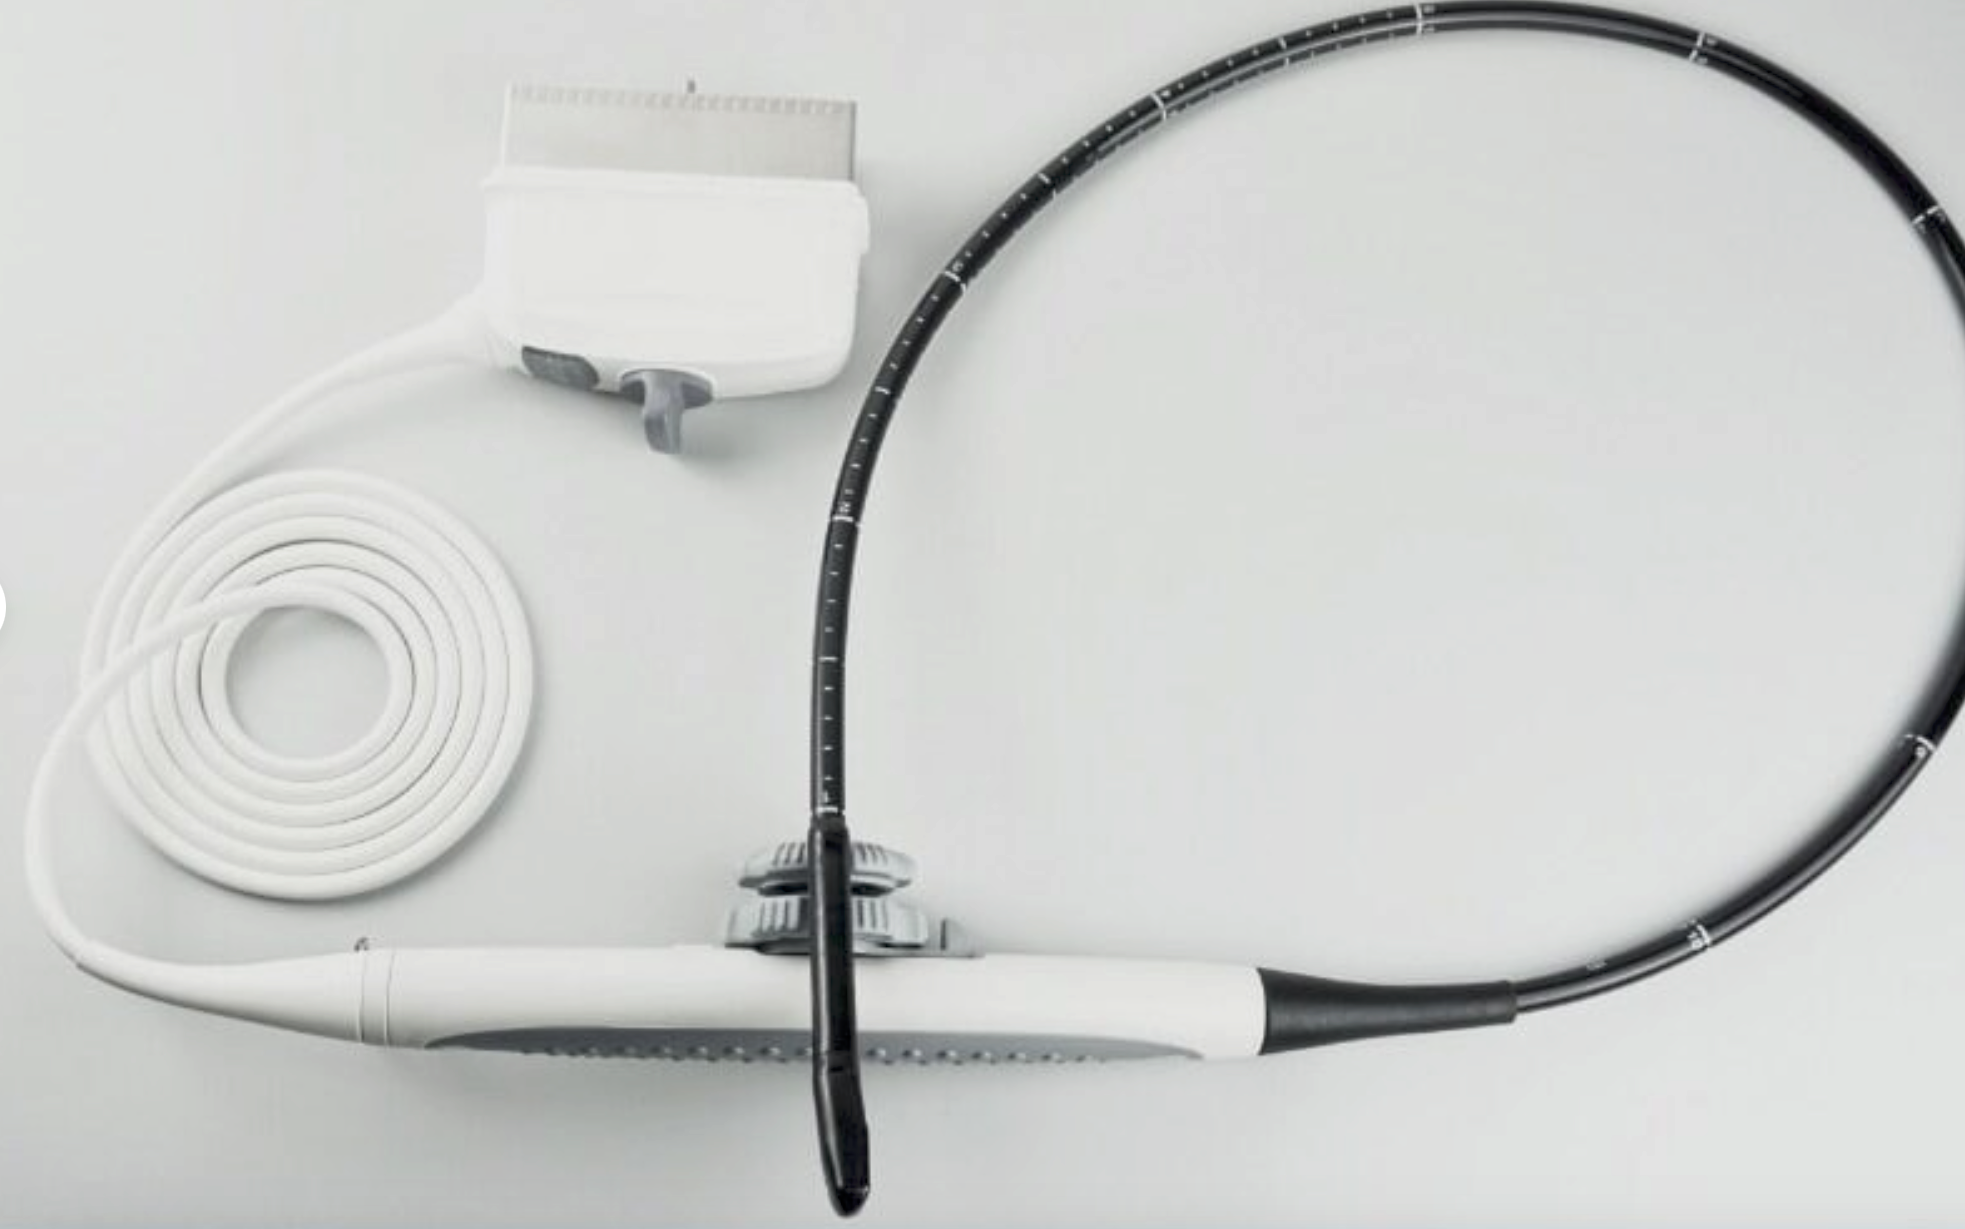

Optional: linear/transvaginal/micro-cardiac/rectal/printer